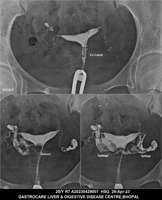

Section: HSG

Total: 49 Cases

All Categories BaM Enteroclysis Loopogram BaE Fistulogram Urethrogram HSG